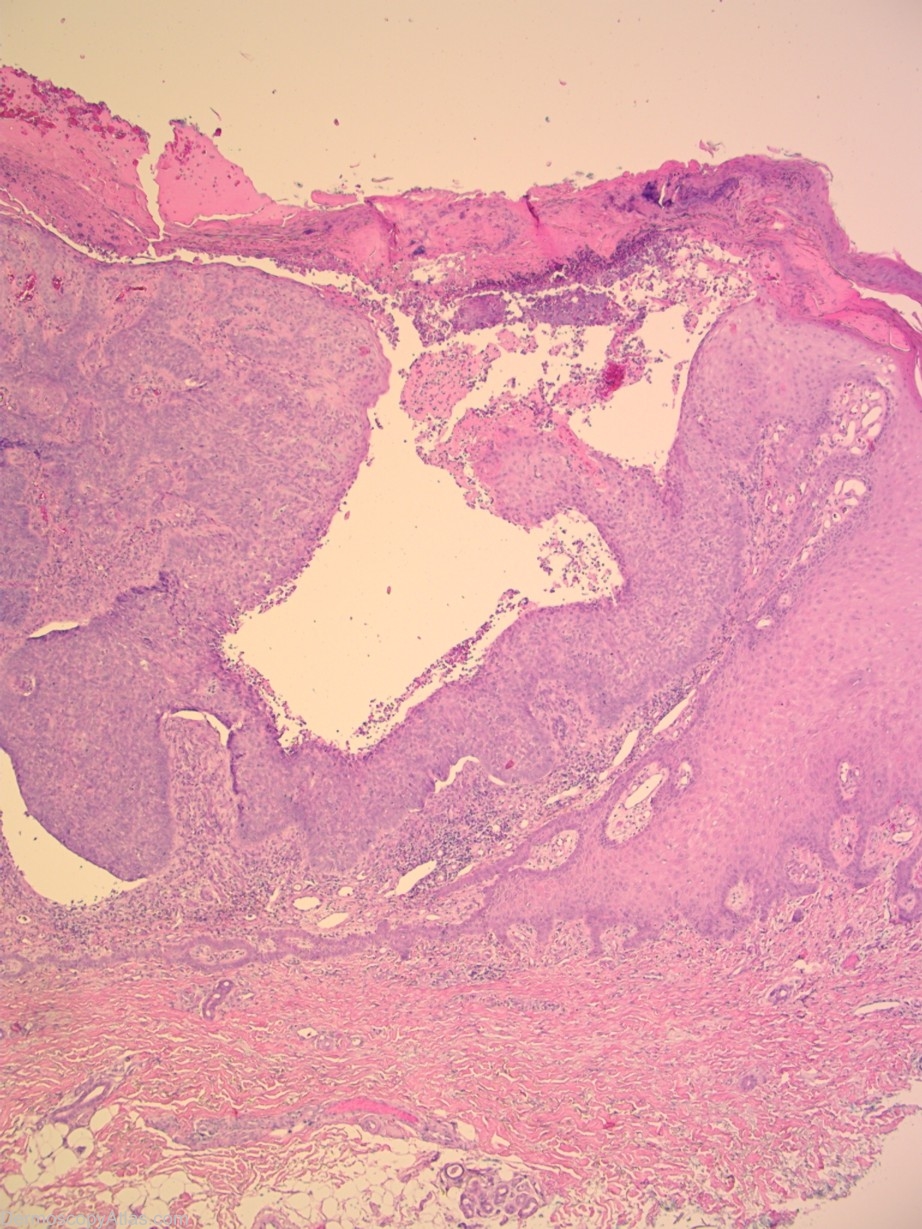

Diagnosis: BCC - Solid

Description: This BCC is ulcerated and displays a variety of blood vessels. There are large arborising vessels as expected in many BCC,s but there are also prominent dot vessels as often seen in melanomas and hairpin vessels as expected in keratinising tumours such as SCC,s. It is a possibility that the severe ulceration present has induced some squamous change resulting in these vessels although such change was not reported by the pathologist.

History: This was an "...ulcerated solid basal cell carcinoma invading to the level of the mid dermis..."The patient reported that there had been a lump at that site for several years but that it had changed recently.